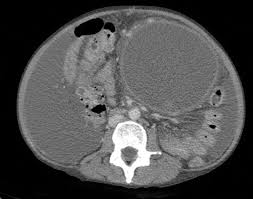

Normally, when i'm on a hunting expedition, (no clue), i would order a ct scan then further imaging as warranted. Note that with some conditions (like suspected gallbladder issues) ultrasound imaging may be the preferred choice. The differential diagnosis for abdominal pain is broad, encompassing gastrointestinal, gynecologic, urologic, vascular, and musculoskeletal conditions. Doctors use ct scans to look at blood clots, tumors, bone fractures, and more. It may be used with or without a contrast dye to see internal structures more clearly.

Ct scans of the abdomen may also be used to visualize placement of needles during biopsies of abdominal organs or tumors or during aspiration (withdrawal) of fluid from the abdomen. There are certain advantages of ct scan like we can make out bony structures better than mri. And the scans i had did not accurately show the soft tissue damage. A ct scan (or cat scan) is best suited for viewing bone injuries, diagnosing lung and chest problems, and detecting cancers. Recently had another mri for another health issue and as a side note when they read the scans they looked at studies suggest that routine imaging for low back pain is a waste of time and money that sometimes harms patients. .into my abdomnal pain i have been refered for a ct scan but can't understand why its not an mri scan insteadi thought mri was much safer than ct as there is mris could be, without letting me decide for myself if i wanted one anyway.i finally was able to get an abdominal and pelvic mri from a sympathetic chiropractor. Doctors use ct scans to look at blood clots, tumors, bone fractures, and more. During a ct scan, a person lies down in a large.

A ct scan (or cat scan) is best suited for viewing bone injuries, diagnosing lung and chest problems, and detecting cancers. The differential diagnosis for abdominal pain is broad, encompassing gastrointestinal, gynecologic, urologic, vascular, and musculoskeletal conditions. The abdomen and pelvis can both be scanned together in one shot with. Learn the similarities and differences in the two scans and how you can prepare abdominal abnormalities: Doctors use ct scans to look at blood clots, tumors, bone fractures, and more. What if the patient in the er insists on an mri to for this reason, wait time and scan times for mri are much longer than ct. We explain the details and differences between ct scans and mris, and help you weigh the benefits and risks of. The person lies on a table that moves through a scanning for mri, people who have trouble with claustrophobia or are unable to hold their breath, which may be required for certain abdominal imaging tests, may not. Like the other 3 tests in this group, the ct scan is painless. Since there is a range of causes for abdominal pain. There are certain advantages of ct scan like we can make out bony structures better than mri. Ct scans of the abdomen may also be used to visualize placement of needles during biopsies of abdominal organs or tumors or during aspiration (withdrawal) of fluid from the abdomen. Why would your doctor recommend one over the other?

Magnetic resonance imaging is another emerging technique for the evaluation of abdominal pain that avoids ionizing radiation. The differential diagnosis for abdominal pain is broad, encompassing gastrointestinal, gynecologic, urologic, vascular, and musculoskeletal conditions. For this reason, wait time and scan times for mri are much longer than ct. Ct scans are widely used in emergency rooms because the scan. Ct scans of the abdomen may also be used to visualize placement of needles during biopsies of abdominal organs or tumors or during aspiration (withdrawal) of fluid from the abdomen. The abdomen and pelvis can both be scanned together in one shot with ct. What are the important differences? Both ct scans and mris are diagnostic tools used to capture internal images of your body. We explain the details and differences between ct scans and mris, and help you weigh the benefits and risks of. These scans can discover any treatment of painful abdomen in cats. Some people refer to a ct scan as a cat scan, which stands for computerized axial tomography. Though the scan is painless, you may have some discomfort from remaining still for several minutes. The ct scan (also called cat scan) is very accurate at examining the adrenal glands and other abdominal structures and can be used on any type of adrenal tumor.